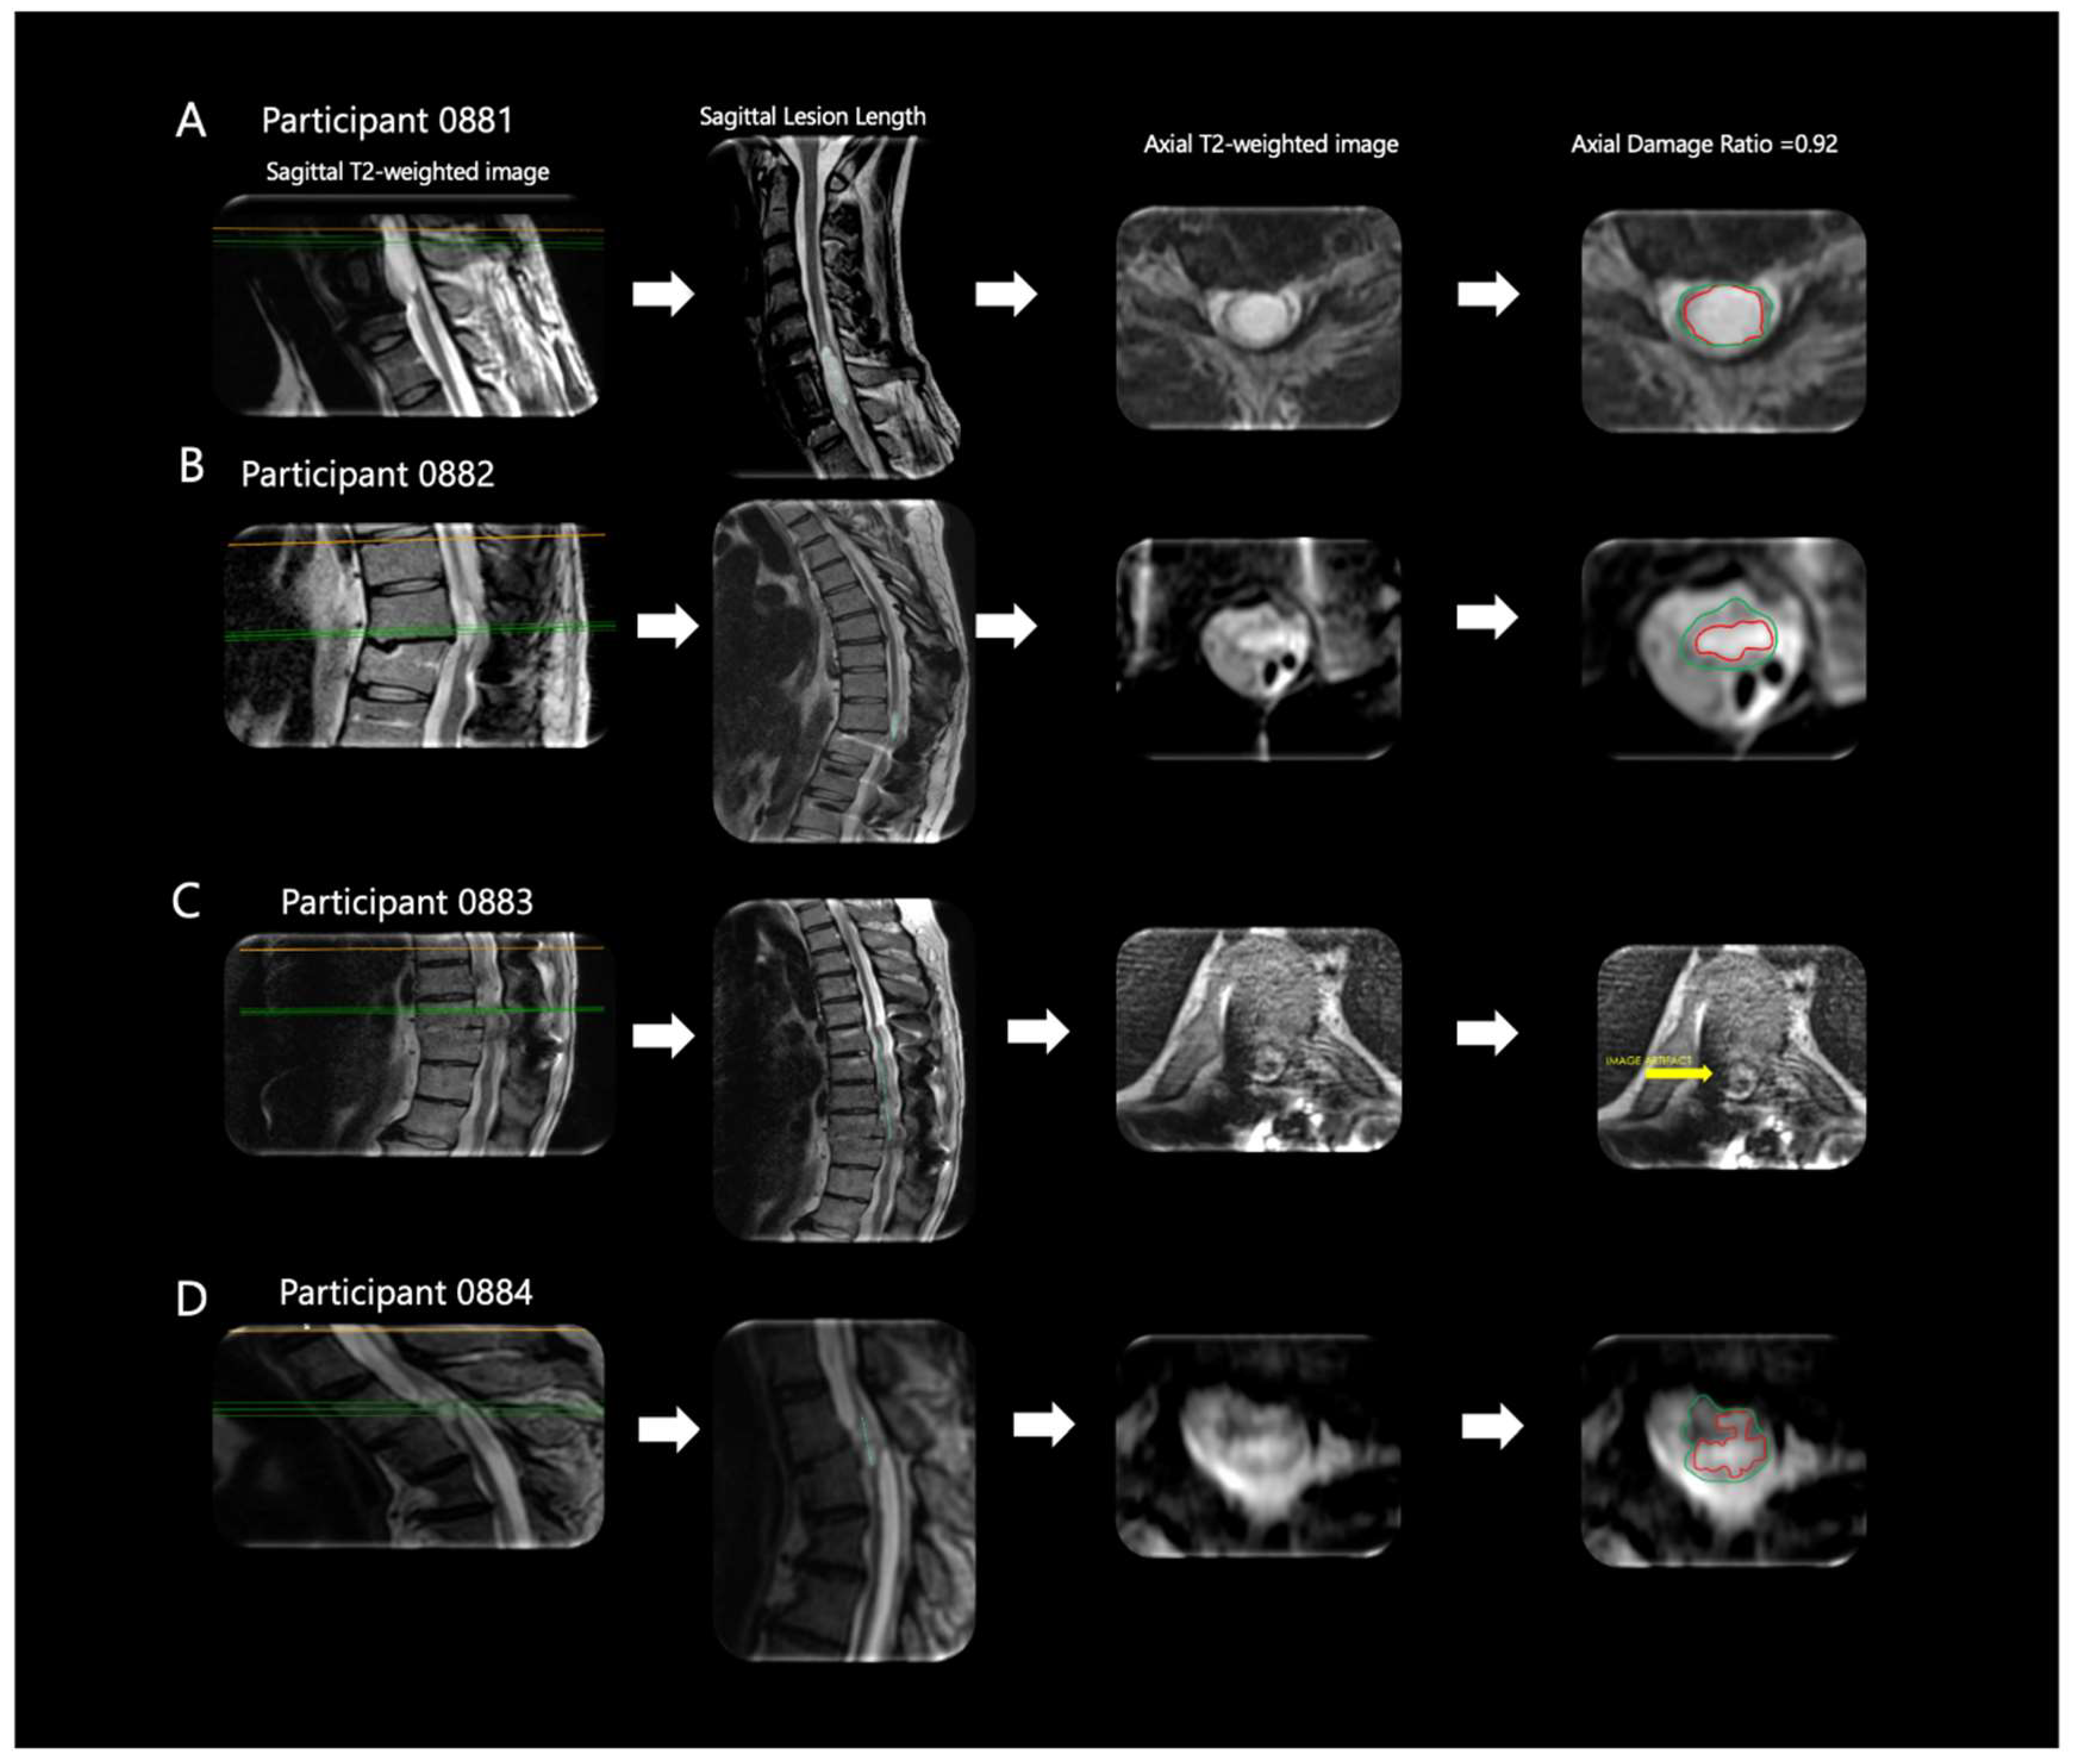

3.1. Magnetic Resonance Imaging (MRI) Biomarkers of Spinal Cord Damage

| ID | Lesion Length (mm) | Lesion Volume (mm3) | Axial Damage Ratio |

|---|---|---|---|

| 0881 | 32.0 | 1932.3 mm3 | 0.92 |

| 0882 | 23.8 | 1881.2 mm3 | 0.81 |

| 0883 | 88.1 | Unable to Assess | Unable to Assess |

| 0884 | 15.5 | Unable to Assess | 0.8 |